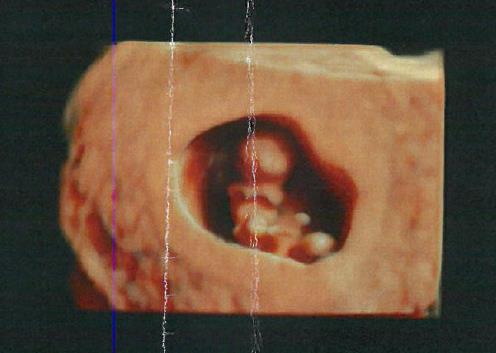

This was taken at exactly 8 weeks! Which was April 7th. I was so happy to see a little baby because when my pregnancy first started we thought I was farther along than I was so when I got an ultrasound it was just a sac which was very scary at the time.